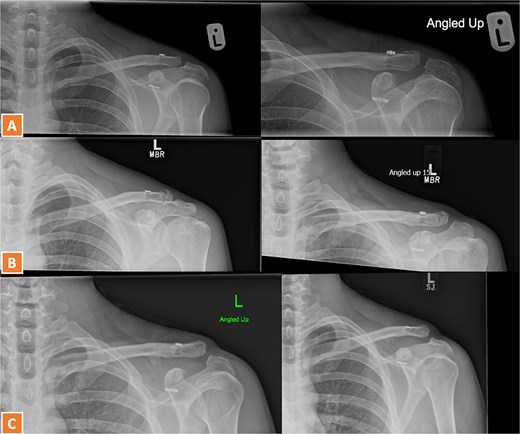

A 27-year-old male suffered a right lateral clavicle fracture after a fall (Fig. 5). He underwent TightRope fixation with stabilization of the coracoclavicular ligament. Rehabilitation was initiated early, and by three months, he had full shoulder motion and returned to overhead sports. Radiographs confirmed union, and the patient reported minor scar sensitivity and transient keloid formation, with no functional limitations (Fig. 6A–D).

Radiographs of third case showing a displaced lateral clavicle fracture with deformity.

(A, B) Radiographs showing healing of the third case and radiological union at 6 weeks and 3 months post-operatively. (C–D) Radiographs showing complete healing of the third case and union at 6 months and 12 months post-operatively.